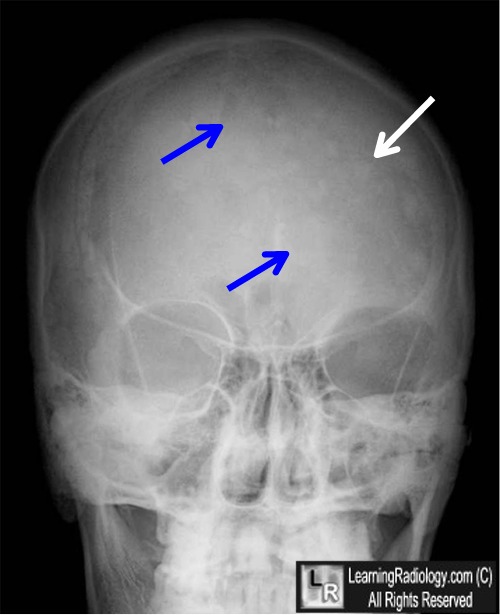

Cotton Wool appearance in Paget Disease There is a thickened calvarium (coarsened trabeculae Cotton Wool Appearance X Ray The cotton wool appearance is a radiographic sign of paget disease, characterized by thickened, disorganized trabeculae and sclerotic patches in bone. Diagnosis is made with radiographs showing characteristic findings of lesions with diffuse blastic appearance and labs showing elevated serum alp and elevated urinary. The blastic, or late inactive,. The cotton wool appearance on radiographs is characteristic. Classic “cotton wool”. Cotton Wool Appearance X Ray.

Xray skull showing cotton wool appearance. Download Scientific Diagram Cotton Wool Appearance X Ray Classic “cotton wool” appearance is caused by irregular areas of focal osteosclerosis as seen in the present case. Diagnosis is made with radiographs showing characteristic findings of lesions with diffuse blastic appearance and labs showing elevated serum alp and elevated urinary. The cotton wool appearance is a radiographic sign of paget disease, characterized by thickened, disorganized trabeculae and sclerotic patches. Cotton Wool Appearance X Ray.

Figure 1 from Paget’s Disease of the Skull A “Cotton Wool” Appearance Semantic Scholar Cotton Wool Appearance X Ray Radiographs of the jaw bones. The cotton wool appearance on radiographs is characteristic. The cotton wool appearance is a radiographic sign of paget disease, characterized by thickened, disorganized trabeculae and sclerotic patches in bone. Diagnosis is made with radiographs showing characteristic findings of lesions with diffuse blastic appearance and labs showing elevated serum alp and elevated urinary. The blastic, or. Cotton Wool Appearance X Ray.